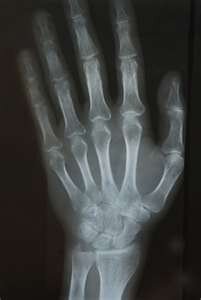

В ноябре 1895 года немецкий физик Вильгельм Конрад Рентгенпроводил эксперимент по изучению люминесценции, которая вызывалась катодными лучами. Для увеличения эффекта он поместил электронно-лучевую трубку и люминесцирующее вещество в черный картонный ящик и наглухо зашторил окна в лаборатории. Включив электронно-лучевую трубку, Рентген неожиданно увидел вспышку света в другой половине комнаты. Оказалось, свет исходил от листа бумаги, покрытого платиноцианидом бария - люминесцирующим веществом. Рентген очень удивился и выключил электронно-лучевую трубку - свечение исчезло. Опять включил трубку - свечение появилось снова. Тогда он перенес бумагу в другую комнату - она продолжала светиться. Ученому стало ясно, что в электронно-лучев ой трубке возникла некая форма излучения, способного проникать не только сквозь картон, но и сквозь стены. У Рентгена не было никаких идей относительно природы этих лучей, поэтому он назвал их икс-лучами (Х-лучами). Рентген занимался Х-лучами около года и опубликовал о них три статьи, в которых было исчерпывающее описание новых лучей, впоследствии сотни работ его последователей, опубликованных затем на протяжении 12 лет, не могли ни прибавить, ни изменить ничего существенного. Рентген, потерявший интерес к Х-лучам, говорил своим коллегам: «Я уже всё написал, не тратьте зря время». Уже другие ученые стали называть их рентгеновскими. За их открытие Рентгену в 1901 году была присуждена Нобелевская премия по физике. Интересно, что наибольшее впечатление на ученых произвела фотография руки, сделанная с помощью Х-лучей. В России лучи стали называть «рентгеновскими» по инициативе ученика В. К. Рентгена — Абрама Фёдоровича Иоффе.